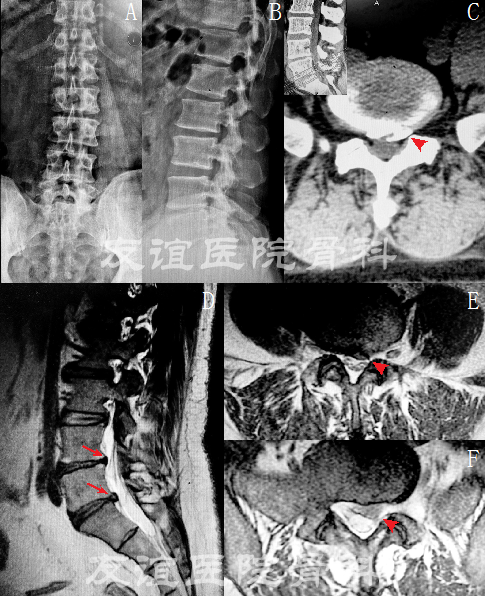

图5:术后1年随访影像学资料:腰椎正侧位片(A,B)

MRI(C-F)提示:L5-S1(F)腰椎间盘突出已经切除

L4-5(D)椎间盘突出明显缓解。(红色箭头标记内植物)